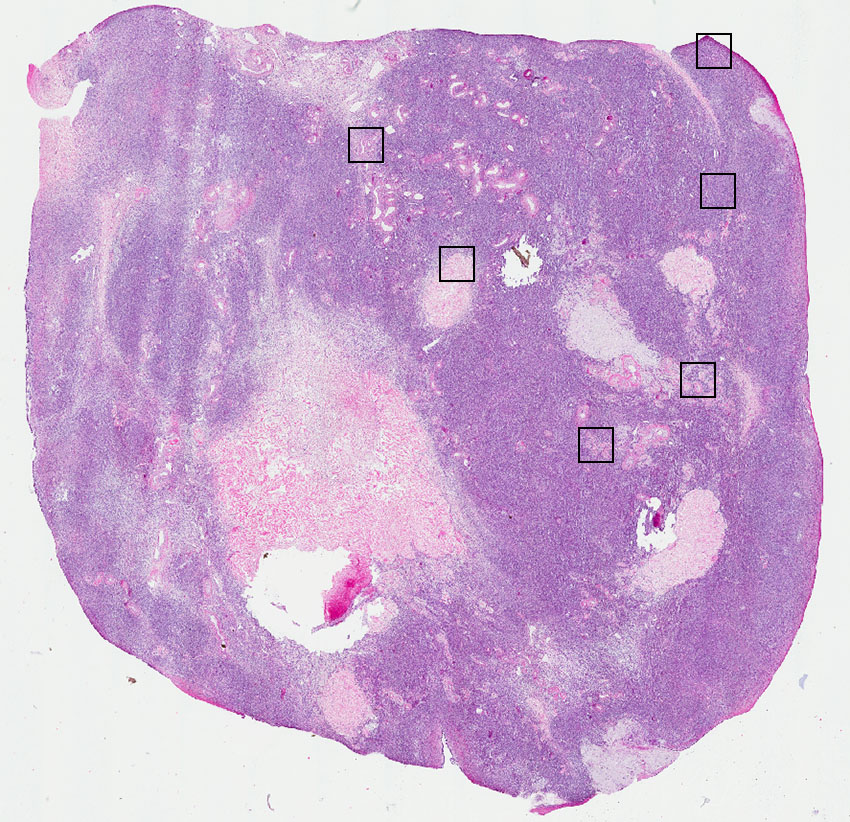

Stromal cells:

95

Other cell types:

5